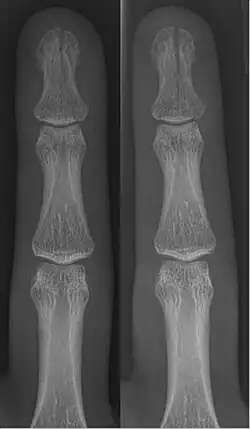

In the fingertip. More images